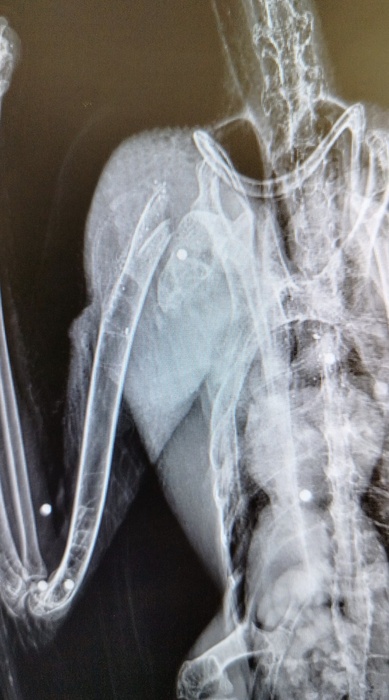

L'ibis ferito è stato trovato in un pollaio dove probabilmente cercava il suo compagno di viaggio. Due, infatti, gli esemplari avvistati in zona nei giorni scorsi. È stato un "cittadino consapevole", ieri, a portarlo al Cras Lago di Penne, che "si è subito attivato portando il giovane esemplare in uno studio veterinario specializzato che ha subito rilevato la rottura dell'omero all'altezza della cintura scapolare e ha effettuato un delicato intervento chirurgico per tentare di restituire all'ala le migliori funzioni per permettere all'Ibis di tornare a volare".

La radiografia ha confermato la "presenza di numerosi pallini da caccia nel corpo del rarissimo animale protetto". Sono stati allertati i Carabinieri forestali del Nucleo Cites, che si occuperanno delle indagini sul "folle atto di bracconaggio", cercando anche di "verificare se l'altro esemplare inseparabile Ibis, di nome 'Coccole', con l'anello numero 751, sia riuscito a sopravvivere".